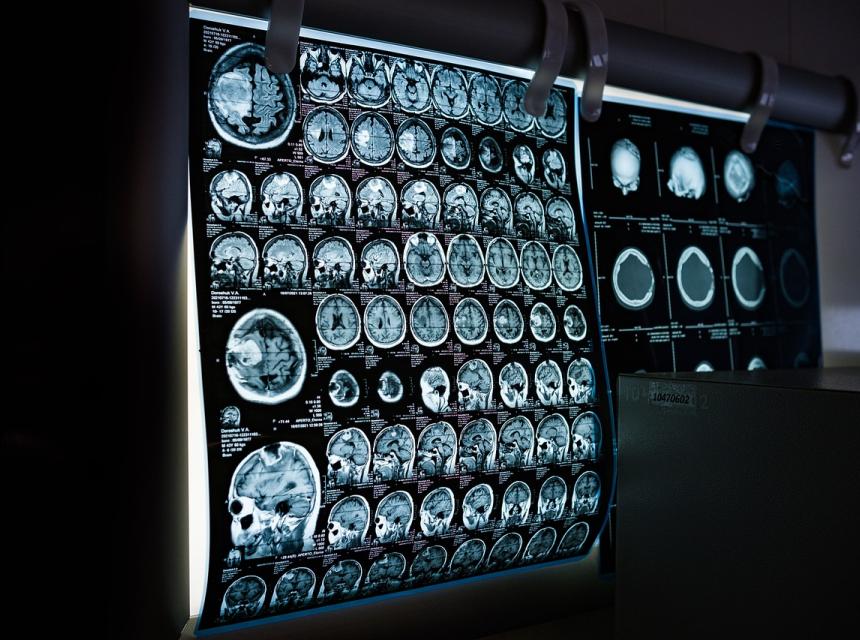

Potíže u mne začaly ke konci roku 2014, kdy jsem začala mít problémy s viděním a rovnováhou. Po neúspěšném ambulantním léčení jsem jela do nemocnice na další vyšetření.